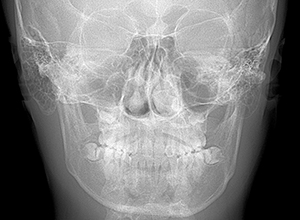

X-Ray

顔貌所見 正貌は左側下顎枝が右側よりもやや長く左側へ偏位しており側貌はconcave typeを呈していた。

セファロ所見 下顎骨は比較的バランスが良いもののセラに対して下顎等は後方に位置しており中顔面部の奥行きもあることから顔面高さは低くなっていた。